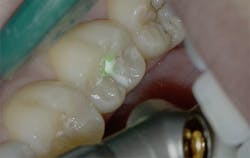

Figure 2: Class I pre-op lesion. Photo courtesy of Jeff Rhode, DDS.

Figure 3: Class I cavity prep after laser. Photo courtesy of Jeff Rhode, DDS.